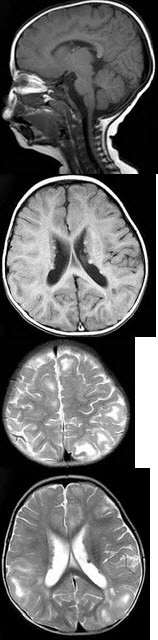

患者,男,1岁。癫痫发作3次,智力反应低下。行头颅MRI扫描如图所示,应诊断为( )

A:颅内结核瘤

B:病毒性脑炎

C:胶质瘤病

D:结节性硬化

E:未见异常